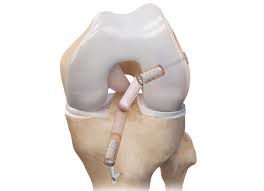

Reconstrucción De Ligamento Cruzado Anterior Por Artroscopia

Paquete de Cirugía: Reconstrucción de Ligamento Cruzado Anterior (LCA)

Equipo y material quirúrgico, incluyendo:

Torre de artroscopia

Insumos para realizar la reconstrucción del ligamento cruzado anterior (sin IVA)

Este paquete está diseñado para ofrecerte una cirugía minimamente invasiva, precisa y segura, enfocada en recuperar la estabilidad de tu rodilla, disminuir el dolor y ayudarte a regresar a tus actividades deportivas y de la vida diaria.